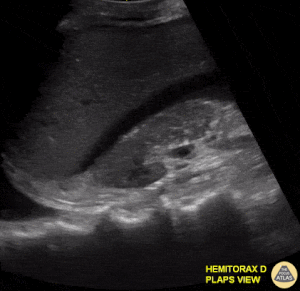

Based on the ultrasound image above, which shock etiology is most likely?

1 pts